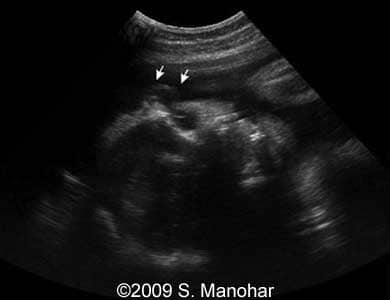

Images 8, 9, 10, 11, 12, and 13: The images shows discontinuities of the skin surface (arrows), a typical sign of the Harlequin type ichthyosis.

8-b

8

9-b

9

10-b

10